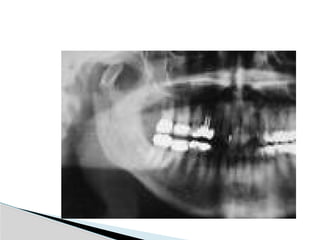

Conventional Radiology

At least 2 views at right angle to each other.

Mandibular series: PA, Lateral oblique or

panoramic, & Towne’s view (projects condyle

below mastoid process).

CT

Significant displacement or dislocation,

mechanical obstruction, mult trauma pt, &

intracapsular fracture.

MRI

St injuries: effusion, visualization of disc.

Imaging

Conventional Radiology At least2 views at right angle to each other. Mandibular series: PA, Lateral oblique or panoramic, & Towne’s view (projects condyle below mastoid process). CT Significant displacement or dislocation, mechanical obstruction, mult trauma pt, & intracapsular fracture. MRI St injuries: effusion, visualization of disc. Imaging